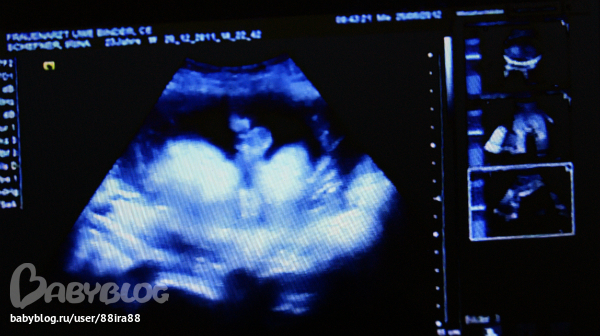

2 последнии 31+4

недели

помню с настей похожее на монитори было)))). врач не может помнить все твои узи ,а на последним узи что то уж слишком длинное ОНО

Я тут еще раз посмотрела.. а не может это быть пуповина на двух последних фотках?)

и мне сказали что девочка на 2х узи в 19+4 недель и в 25 недель а вот в 31 сказали кажется мальчик но не точно